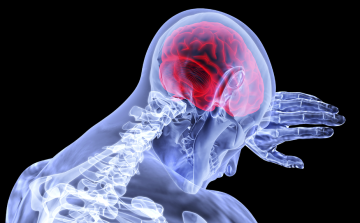

Néhány hónapon belül kiderülhet, hogy érinti-e a fertőzés az agyat

Néhány hónapon belül kiderülhet, hogy a koronavírus-fertőzés érinti-e az agyat, és ha igen, mely területeit - mondta Dénes Ádám, a Kísérleti Orvostudományi Kutatóintézet (KOKI) munkatársa az M1 csatornán csütörtök este.